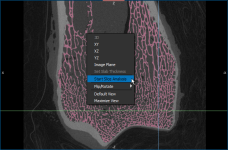

- Right-click the required 2D view of the region of interest and then choose Start Slice Analysis in the pop-up menu.

The Slice Analysis panel appears on the right sidebar (see Analyzing Slices).

- Select the region of interest that you want to analyze in the Object studied drop-down menu, as shown below.